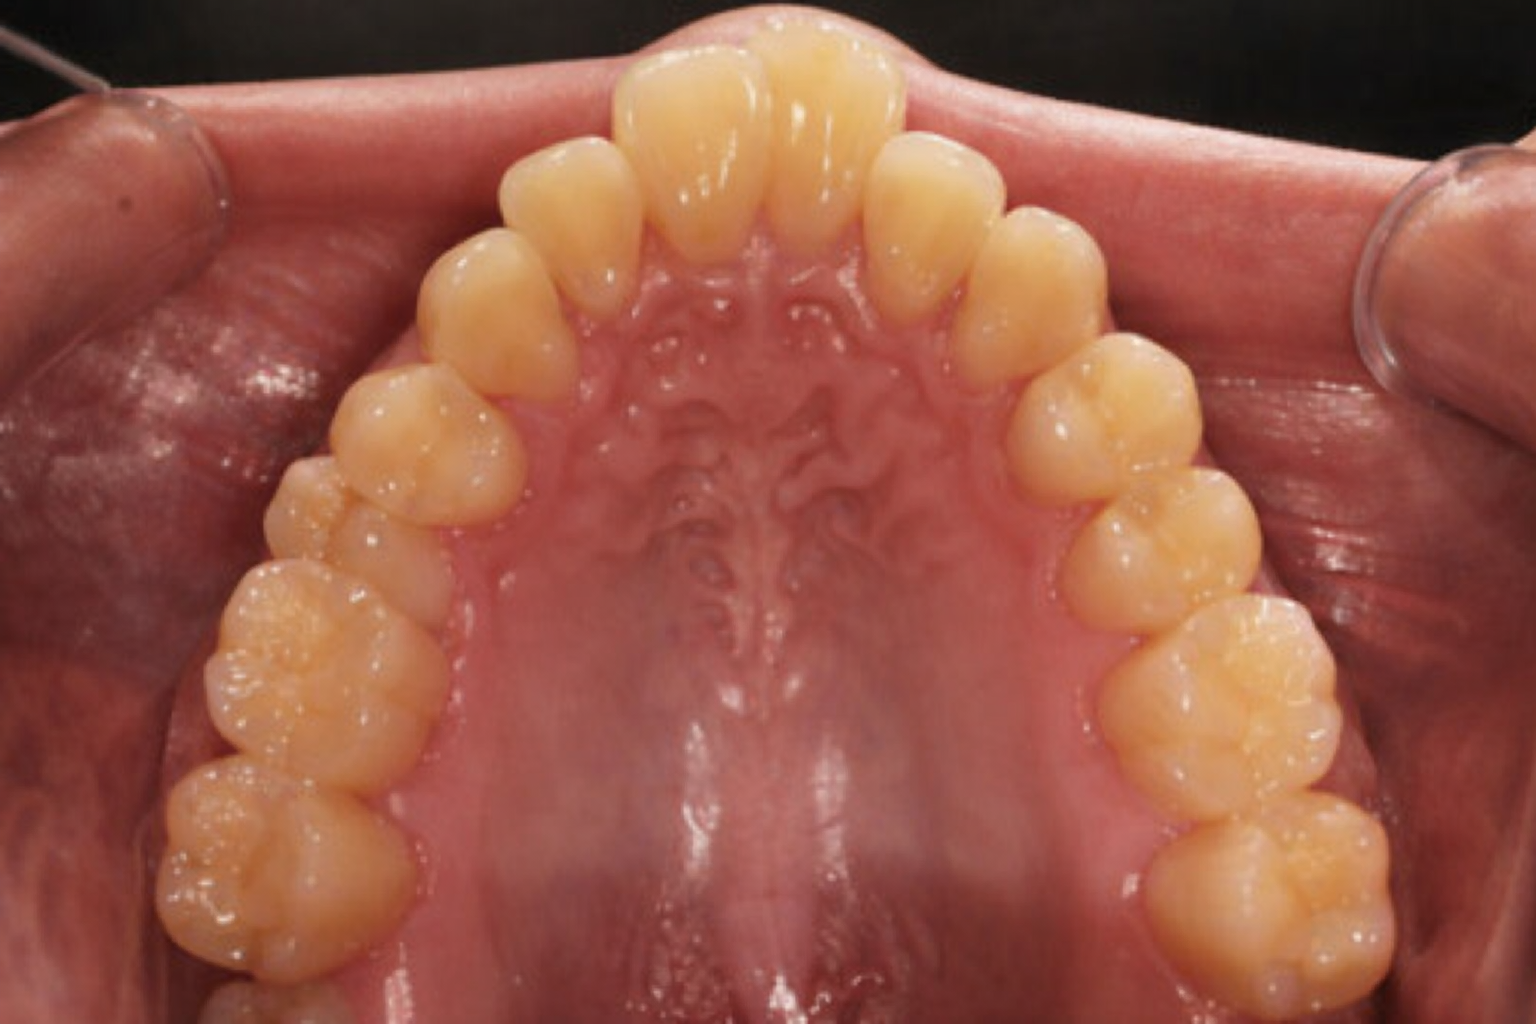

구호흡이 지속되면 혀가 구개에서 떨어져 상악을 안쪽에서 지지하는 힘이 약해집니다. 그 결과 치열궁 폭경이 좁아지면서 치아가 들어설 공간이 부족해지고, 총생(덧니)으로 이어지는 경우가 많습니다. 이 상태에서 구호흡을 해결하지 않고 교정을 먼저 시작하면, 치료 후에도 같은 문제가 반복될 수 있습니다.

개방교합이나 총생이 있는 경우, 구호흡이 그 원인 중 하나였을 가능성이 있습니다. 치아 배열만 교정해도 개선은 되지만, 구호흡 원인을 함께 평가하지 않으면 같은 문제가 반복될 수 있습니다.

A. 세팔로 방사선 사진과 기도 분석, 구강 근기능 검사 등을 통해 구호흡과 부정교합의 연관성을 평가할 수 있습니다. 상악 협착, 개방교합, 수직 성장 패턴 등이 동반된 경우 구호흡의 기여도가 높을 수 있으며, 정밀 검사 후 치료 방향을 안내해 드립니다.